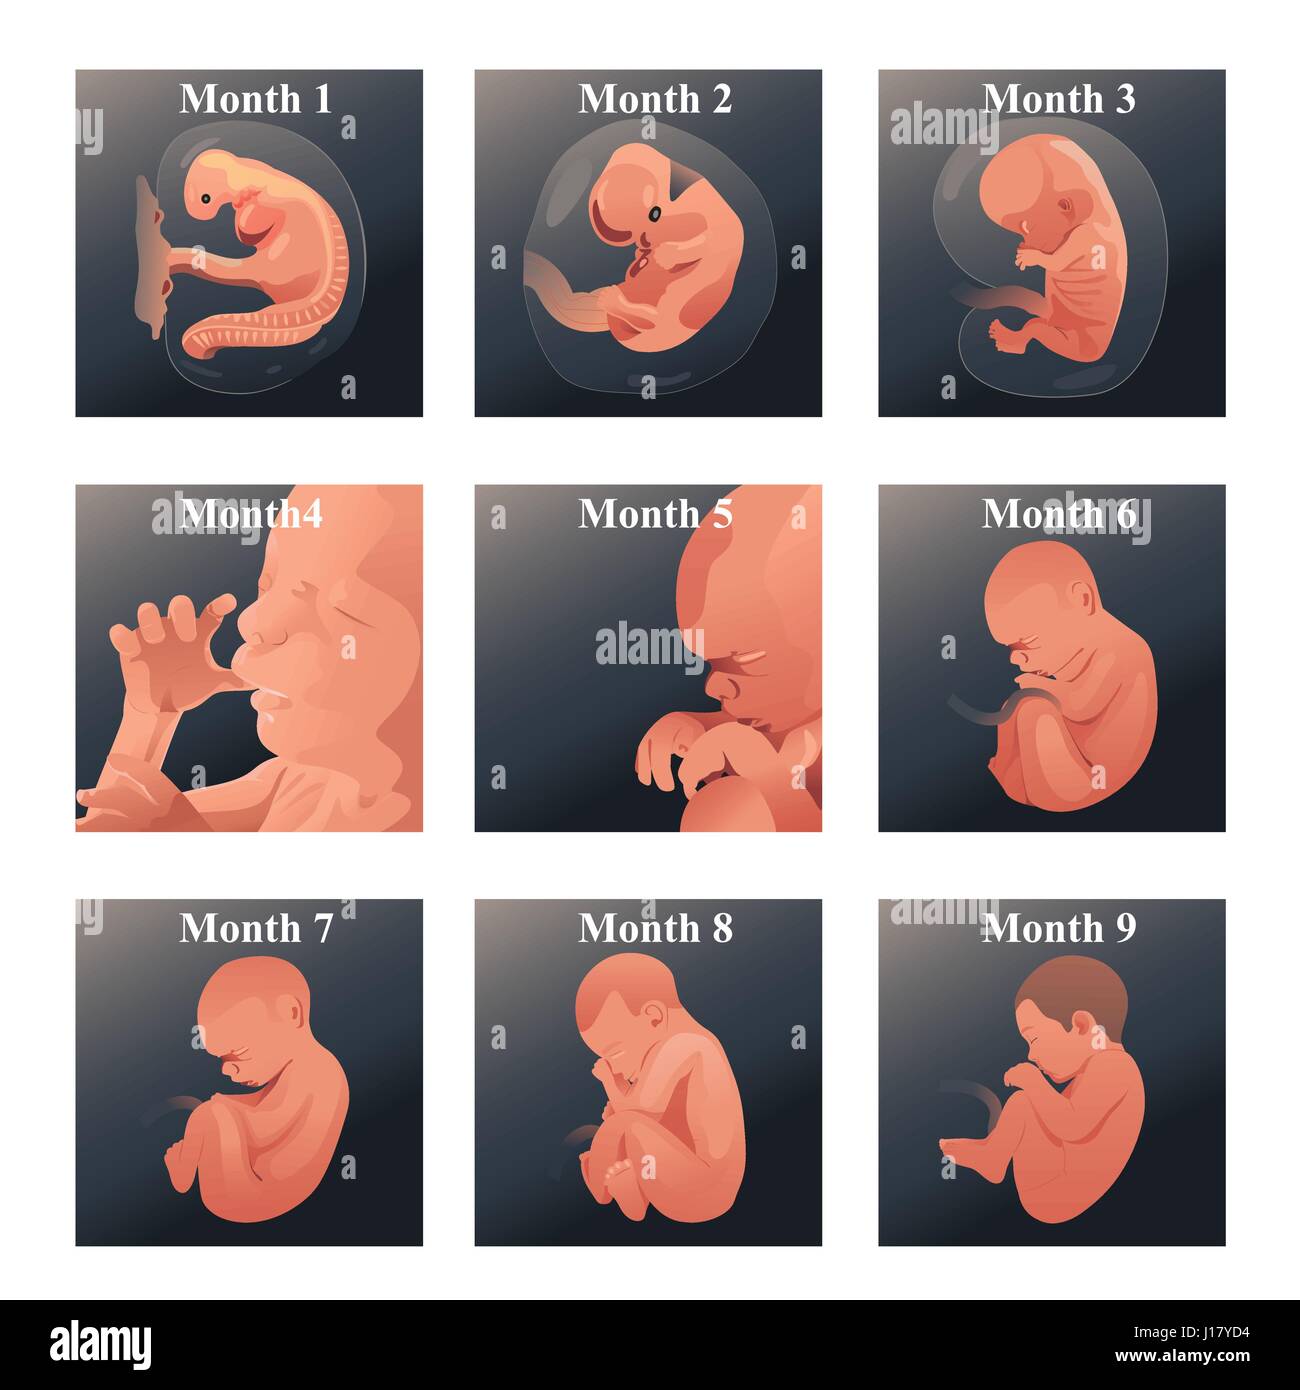

Looking for captivating what does a 2 month old fetus look like images? All, in collaboration with felix.edu.vn, presents a curated selection. Dive into the details for more.

what does a 2 month old fetus look like

We hope you enjoyed this article about what does a 2 month old fetus look like on felix.edu.vn. Let us know what you think in the comments, and discover more related content below.